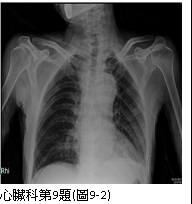

9. 男性病人,72歲,因尖銳性上背部疼痛突然發作,同時伴有急促呼吸及眩暈,乃往急診求治。時,血壓149/91 mmHg;心跳,70/min; RR, 20/min;其他理學檢查並無任何異常。病人每天抽煙一包,已有五十多年。Chest X-ray、ECG及CT,如圖9-1、圖9-2、圖9-3A及圖9-3B後,及其初步處置,後轉送加護病房途中,又突發後背疼,同時雙腳麻及疼痛,並呈現雙腳發紺,乃急照另次CT如圖9-4所示。請問下列何者決策不恰當? (A) 控制心收縮血壓在100-120 mmHg及心跳60-80/min (B) 靜脈注射Labetalol 30 mg/min (C) 口服Propranolol 20 mg tid po (D)口服Aspirin 100 mg qd 及Clopidogrel 75 mg qd (E) 外科會診,緊急手術